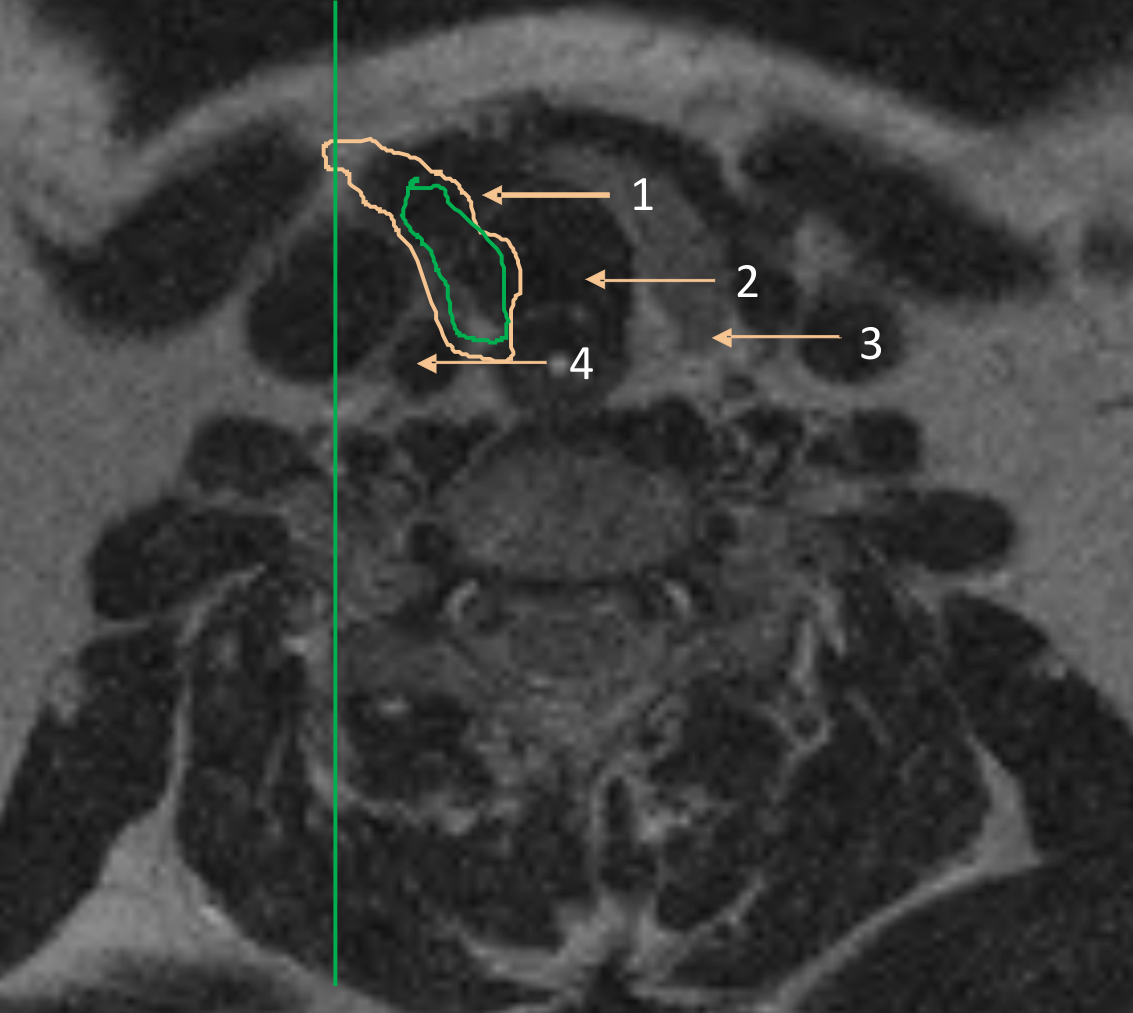

Первый тип характеризовался смещением пищевода к задней поверхности боковой доли, сосудисто-нервного пучка – по латеральной поверхности доли кпереди (рис. 1).

Рис.1. Переднелатеральный тип смещения. Диспозиция пищевода к задней поверхности левой доли щитовидной железы, сосудисто-нервного пучка – по латеральной поверхности доли кпереди: 1 – доля щитовидной железы; 2 – общая сонная артерия; 3 – внутренняя яремная вена; 4 – пищевод